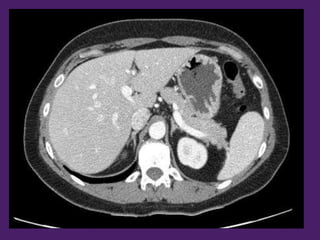

Aorta

descendente

Vena cava

inferior

Lóbulo

derecho

del hígado

Recto del

abdomen

Fundus

gástrico

Bazo

Arteria

esplénica

Vena esplénica

izquierdo

Pilares del

diafragma